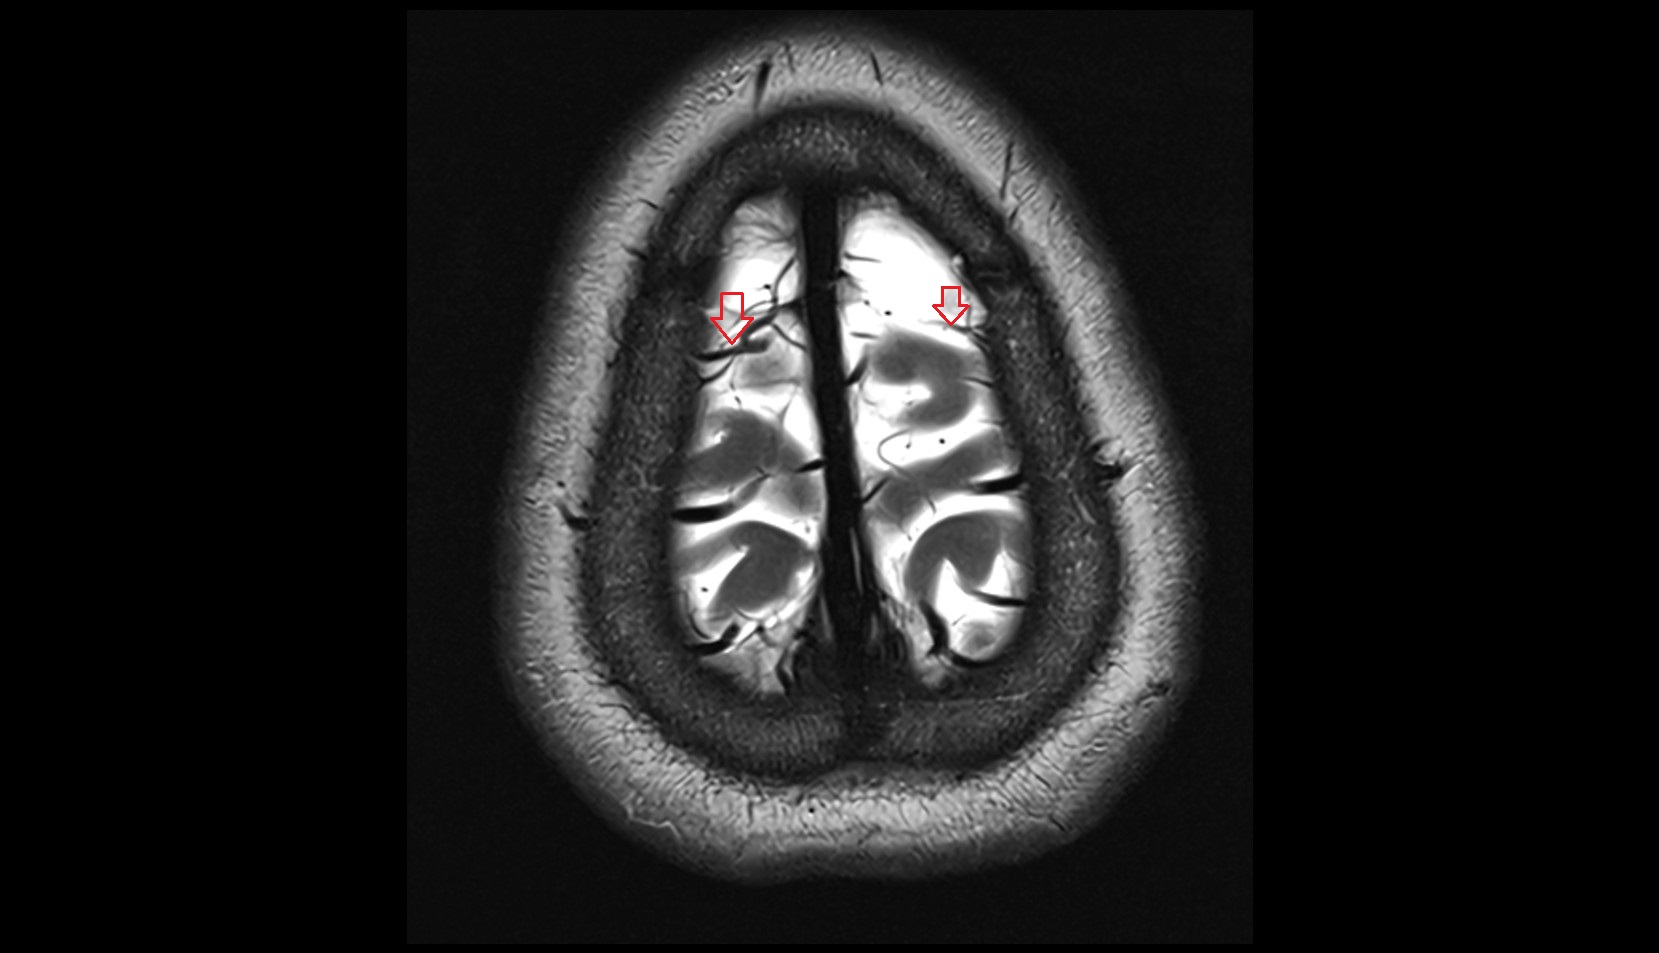

- Superficial cerebral veins

- Superior anastomotic vein

- Superior sagittal sinus

- Superior cortical veins